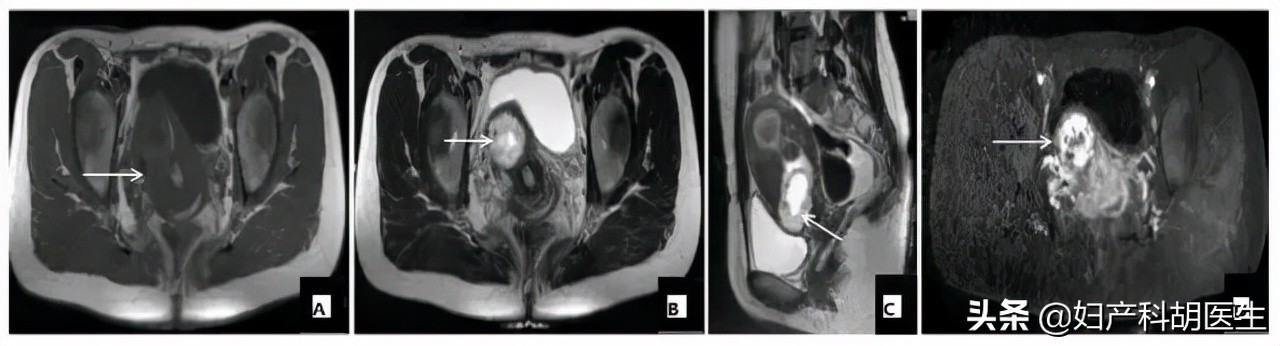

B 超是诊断瘢痕妊娠的首选,也是最重要的一项检查,腹部超声结合阴道超声,当超声诊断有难度时,可行 MRI 检查协助诊断。

下面是一个子宫瘢痕妊娠患者的 MRI 图像,与 B 超相比,MRI 对孕囊的位置、子宫肌层的显示较为清楚。

图 A 子宫前下壁偏右侧肌层内见混合信号妊娠囊,19 mm×21 mm(箭头所指);图 B 子宫前壁肌层明显受浸润(箭头所指)。图 C 前方子宫肌层几乎消失(箭头所示)。图 D 胚胎组织与子宫肌层分界不清,提示子宫肌层受到浸润,子宫壁即将穿破(箭头所示)。